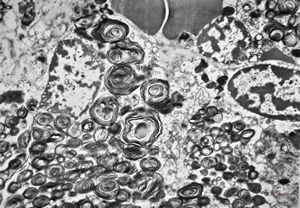

M, 44y. | Gaucher disease … liver